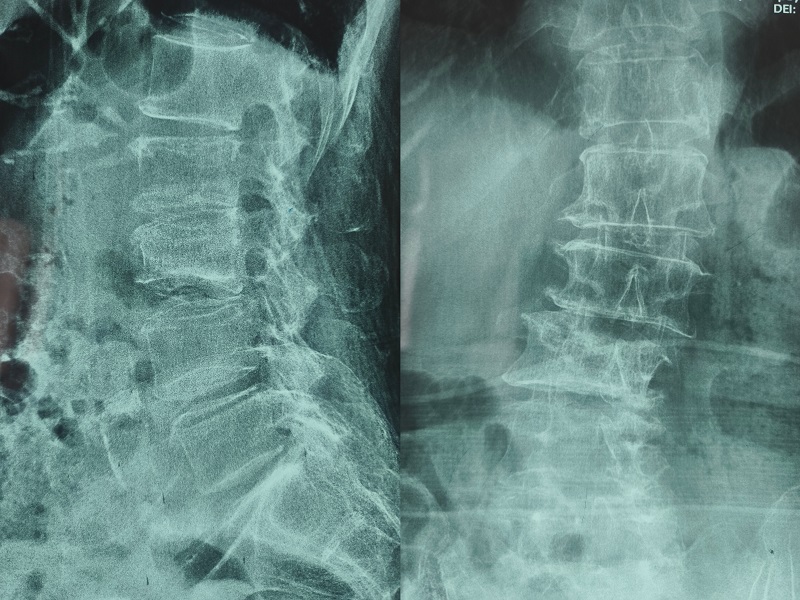

術(shù)前圖像